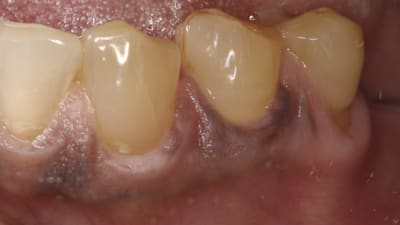

Case Reports Restorative Direct Restorative Minimally Invasive Dentistry: A Conservative Approach to Smile Makeover By Jeffrey M. Rosenberg, DDS January 01, 2017 14 min read